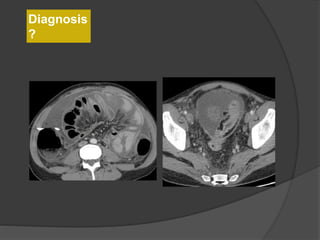

Diagnosis

?